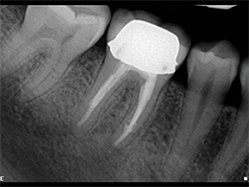

Slika 6:Vitalni prvi gornji molar sa ireverzibilnim pulpitisom. Uočljiv je izrazito dugačak palatinalni kanal (oko 31mm),koji je ipak zapečaćen zajedno sa petljom lateralnog kanalom zahvaljujući dobroj hemijskoj obradi kanala koja je omogućila kompaktnost punjenja.